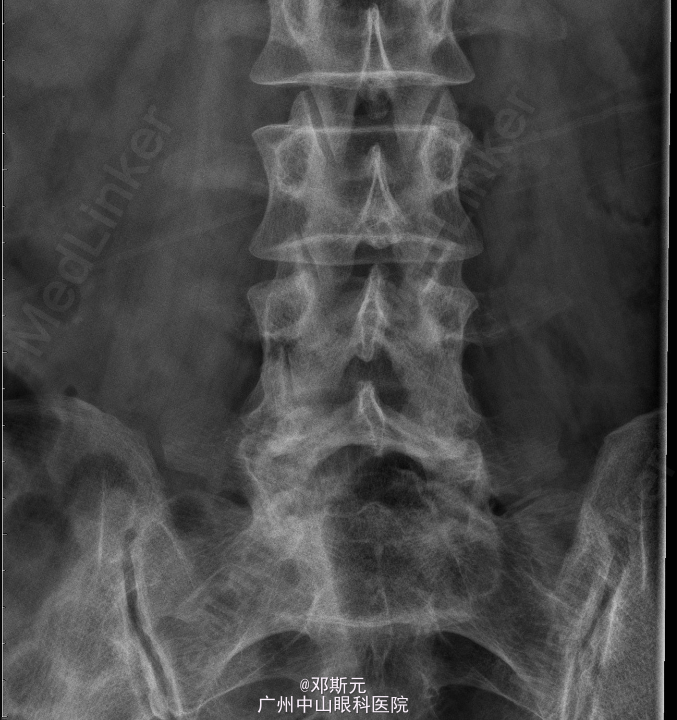

患者,女,47岁,主因“反复腰痛伴双下肢痛3月,加重20天”入院。 患者3月前无明显诱因出现反复出现腰痛,伴右下肢麻痛,以股外侧明显,疼痛影响活动,步行百米后便需要休息,休息后可自行缓解,左侧不明显,外院行理疗治疗后缓解。20天前无明显诱因下出现腰痛伴左下肢麻痛,右侧麻痛不明显,遂到外医院查MRI见腰4椎体滑脱,后为作进一步治疗到我院求医,门诊拟“腰椎滑脱症”收入我科。

查体:腰椎活动受限,双侧屈曲激发下肢放射性麻痹,腰4棘突叩击诱发左下肢麻痹,椎体棘突局部无压痛叩痛,左臀、左大腿外侧感觉稍差,余无异常。 辅助检查:外院腰椎MRI见:腰4椎体滑脱,L2/3至L5/S1椎间盘突出,L4/5椎间盘突出伴髓核脱出。L5/1椎间盘邻近椎体终板炎可能。腰椎退性变。

诊断:腰椎滑脱症(L4);腰椎间盘脱出症(L4/5);腰椎间盘突出(L2/3、L3/4、L5/S1)。术前检查未见明显异常,全麻下行“腰椎滑脱复位、椎间盘切除、椎弓根螺钉内固定、植骨融合术”。